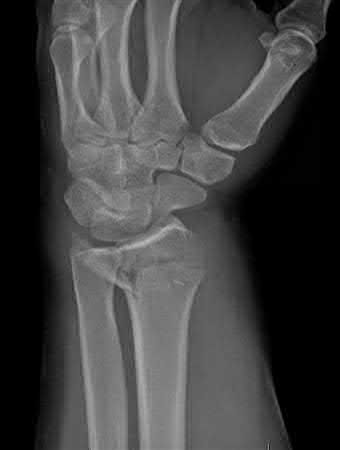

A 38-year-old male suffers the injury shown in Figure A. During operative fixation, free osteoarticular fragments are encountered and reconstruction of these pieces is attempted. Postoperatively, which of the following will have the most beneficial effect on the healing potential of the surviving chondrocytes within these reconstructed articular segments?

Figure A demonstrates a comminuted tibial plateau fracture with significant intra-articular involvement. Basic science evidence has demonstrated that post-operative gentle compressive loading may have a positive impact on articular cartilage healing; however, excessive shear loading may be detrimental.

Irrgang et al provide guidelines for rehabilitation following surgical management of articular cartilage lesions of the knee. They state that after articular cartilage repair, exercises to enhance muscle function must be done in a manner which minimizes shear loading of the joint surfaces in the area of the lesion. The authors also discuss the benefits of gentle compressive loading and motion of the joint, and its positive effects on chondrocyte nutrition.

Furthermore, they recommend a period of protected weight bearing as often being necessary, and that this should be followed by progressive loading of the joint.